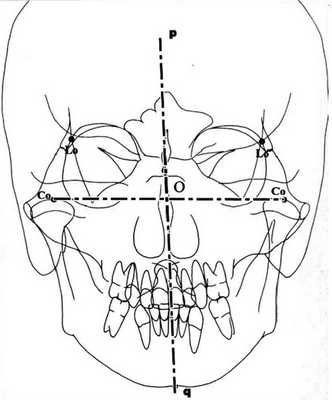

4. Построение сагиттальной оси НЧ и то, почему оно необходимо, мы объясним ниже. Соединяем уже отмеченные точки Со-Со и из середины полученного таким образом сегмента (точка О) опускаем перпендикуляр, который является сагиттальной осью мандибулы. Обозначим ее pq (рис.3). Рисунок 3. Построение сагиттальной оси НЧ.

Обоснование. Созданная нами методика оценки трансверсальных несоответствий лицевого отдела черепа была продиктована неточностью анализа симметрии НЧ. Является ли НЧ симметричной или нет, обычно определяют по средней сагиттальной оси черепа, но иногда это может ввести в заблуждение. Например, НЧ может быть симметричной, но при ротации в суставах точка Ме перемещается с лицевой оси MSR, что позволяет сделать неверный вывод об асимметричности НЧ. Мы рассматриваем НЧ в качестве отдельного объекта, имеющего свою собственную сагиттальную ось (pq), так как нельзя определять симметричность одного тела (НЧ) относительно сагиттальной оси другого тела (черепа): это приводит к 2 системам координат: 1 — черепа (MSR по V. Sassounni), другая — НЧ (pq) (рис. 5, см. на цв. вклейке). Рисунок 5. Компьютерная графика 2 сагиттальных осей MSR и pq.

При взаимном расположении 2 ординат, которые являются осями симметрии этих 2 объектов (череп и НЧ), возникают 4 варианта: обе оси объединены; одна ось повернута относительно другой; оси параллельны друг другу; оси сдвинуты и повернуты относительно друг друга.

В зависимости от ситуации точка Ме может находиться или не находиться на оси симметрии челюсти (pq), параметры удваиваются, т.е. мы получаем 8 графических моделей.